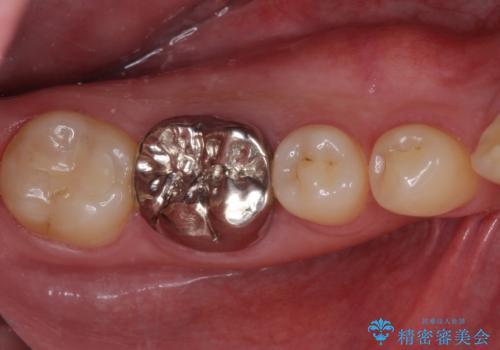

奥歯の目立つ銀歯が気になる 奥歯のセラミッククラウン

- 口を開けたときに目立ってしまう銀歯をセラミックに替えたいとのことで来院された患者様です。

以前むし歯治療を受けたときは時間がなかったため、近医で銀歯を入れたようですが、周囲の目線が気になるとのことでフルジルコニアクラウンにて補綴することとしました。